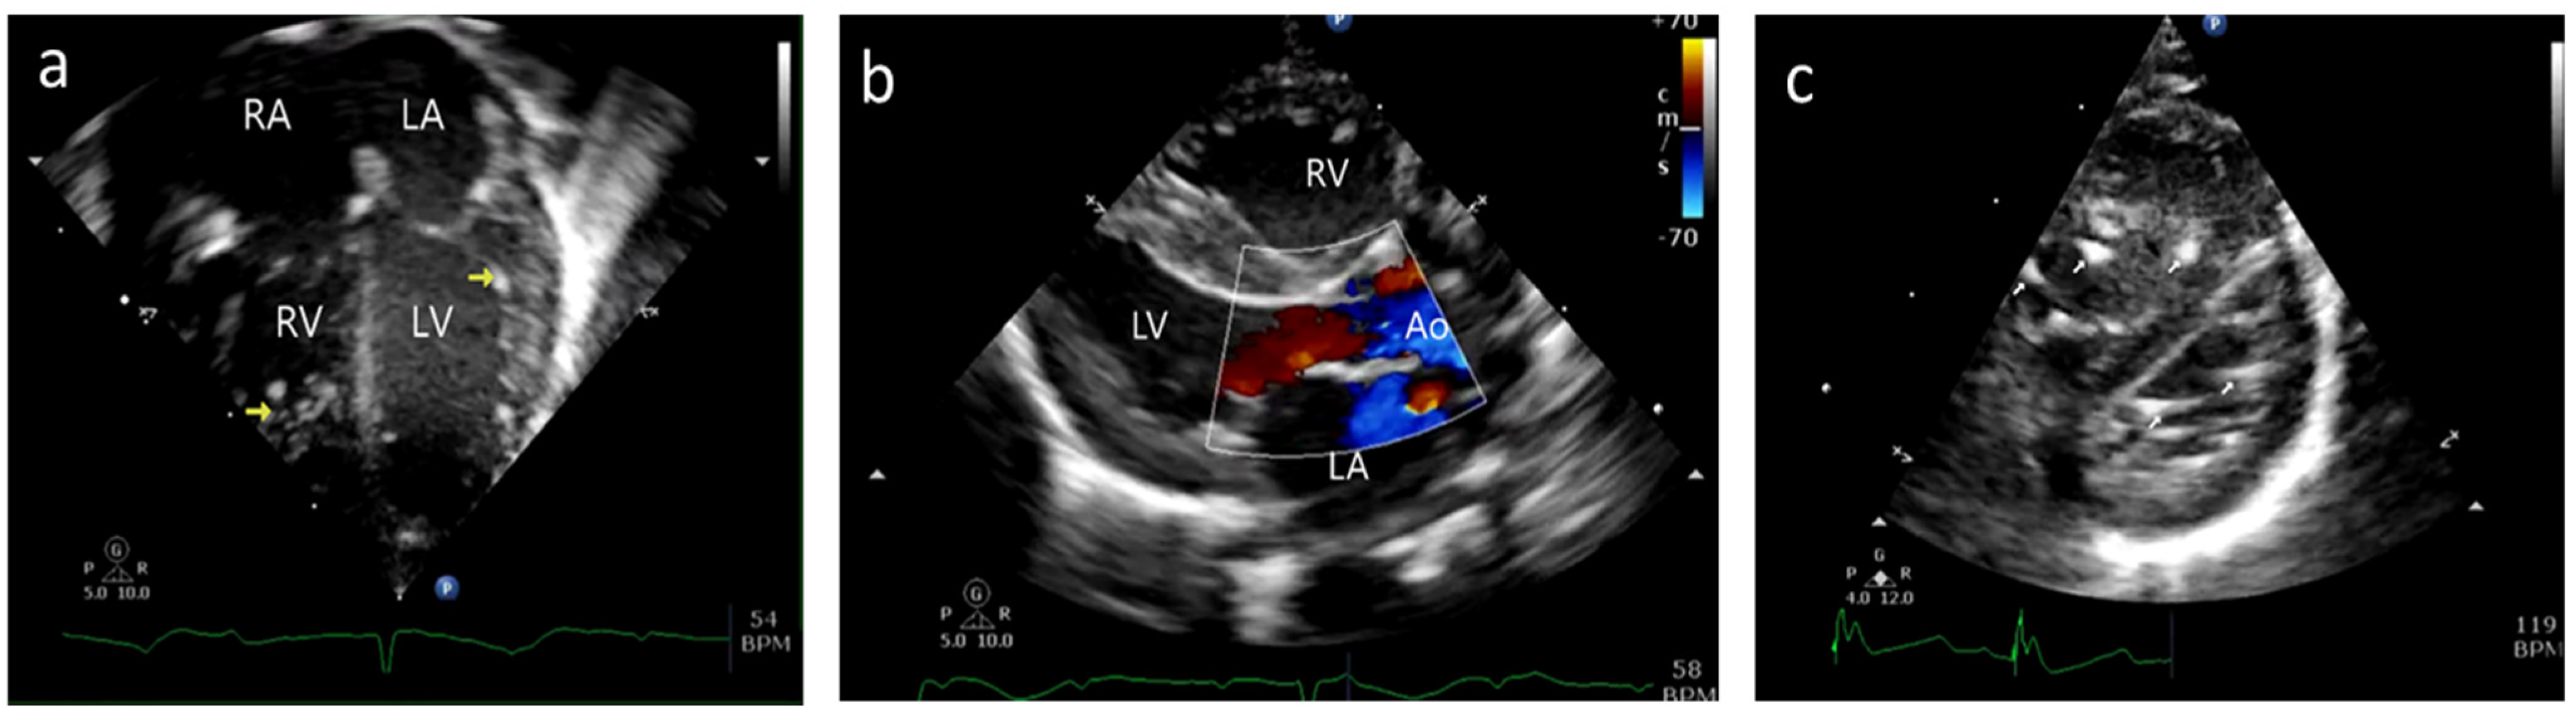

Case A: (a) Postnatal echocardiogram—four-chamber view showing normal mitral and tricuspid valves. Hyperechoic papillary muscles (yellow arrow) were noted. RA—right atrium, LA—left atrium, RV—right ventricle, LV—left ventricle. (b) Immediate postnatal echocardiogram, long axis view, showing no regurgitation of the mitral valve. Ao—Aorta. (c) Postnatal echocardiogram, short axis at the level just below the mitral valve, showing hyperechoic papillary muscles in the left (bottom) and right (top) ventricles (white arrow).

However, on day 45 of life, the baby developed acute respiratory distress and lactic acidosis, requiring inotropic infusion. The septic workup was negative; however, anti-Ro titers were positive. An echocardiographic evaluation showed moderate TR and severe MR. Flail mitral and tricuspid valve leaflets were noted with ruptured chordae resulting in valve prolapse and severe regurgitation (Figure 4/Videos S6–S11). Pleural and pericardial effusions were present with hepatic dysfunction and seizures while on steroids and inotropic supports. The neonate expired at 55 days of age.

Figure 4.

Case A: (a) Echocardiogram, four-chamber view with color doppler showing severe tricuspid regurgitation (pink arrow) and severe mitral regurgitation (green arrow) noted on day 45 of life. (b) Echocardiogram, four-chamber view, demonstrating ruptured chordae resulting in prolapse of tricuspid valve leaflets (white arrow) and mitral valve leaflets (pink arrow). *—Pericardial effusion. (c) 2D and color doppler long axis views of the mitral valve showing valve prolapse (pink arrow in 2D image) and severe mitral valve regurgitation (white arrow in color image) (d) Modified long axis view on a 2D echocardiogram, showing rupture of the tricuspid valve chordae (pink arrow) and severe tricuspid regurgitation (white arrow). (e) Echocardiogram, four-chamber view of ruptured mitral valve leaflet chordae causing mitral valve prolapse (white arrow). (f) X-plane color doppler image on a 2D echocardiogram showing severe mitral regurgitation (black arrow).